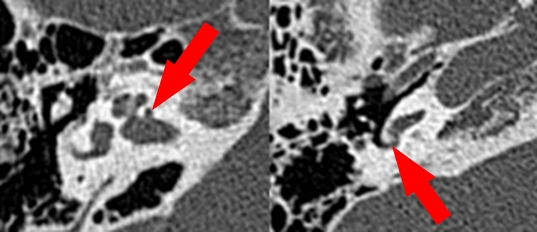

이에 송재진 교수팀은 수술을 시행하기 전 CT 검사 소견을 통해 등골 수술로 실제 청력을 향상시킬 수 있을지 여부를 미리 예측하고자 했다. 특히 최근 발견된 새로운 형태의 이경화증인 ‘공동성 이경화증’(병변이 내이도까지 침범한 형태)이 수술 결과에 미치는 영향에 대해서도 함께 연구했다.

이를 위해 연구팀은 분당서울대병원에서 2004년부터 2017년까지 등골 수술을 받은 진행성 이경화증 환자 중 17명의 CT 소견과 수술 전후 청력 검사 결과를 분석했다. CT 검사에서 진행성 이경화증이 침범한 해부학적인 구조물을 위치별로 파악하고, 공동성 이경화증이 존재하는지 여부도 함께 평가했을 때, CT에서 확인되는 침범된 구조물에 따라 수술 후 청력 검사 개선도가 다른 것으로 나타났다.

연구결과에 따르면, 공동성 이경화증이 있을 때, 달팽이관과 정원공, 반고리관에 침범이 있는 경우 수술 후 청력이 유의미하게 낮은 것으로 드러났다. 또한 이경화증 환자의 수술 성공 여부의 척도가 되는 공기와 뼈의 전도 차이 개선은 정원공의 침범과 공동성 이경화증이 있는 경우에 특히 나쁜 것으로 밝혀졌다. 공기와 뼈의 전도 차이가 10 dB 이상으로 줄어드는 것을 수술 성공의 척도로 삼았을 때, 정원공의 침범이 있는 경우 그렇지 않은 경우에 비해 청력 개선에 실패할 확률이 무려 19배였으며, 공동성 이경화증이 있는 경우에는 실패할 위험성이 약 13배에 달했다.

정원공에 침범이 있는 환자는 난원공에서 정원공으로 전달되는 소리의 전도가 약해지는 ‘단일 창 효과’로 인해, 공동성 이경화증 환자는 소리의 전도가 공동성 병변을 통해 빠져나가는 ‘제 3의 창 효과’로 인해, 각각 청력 개선에 방해를 받았다.